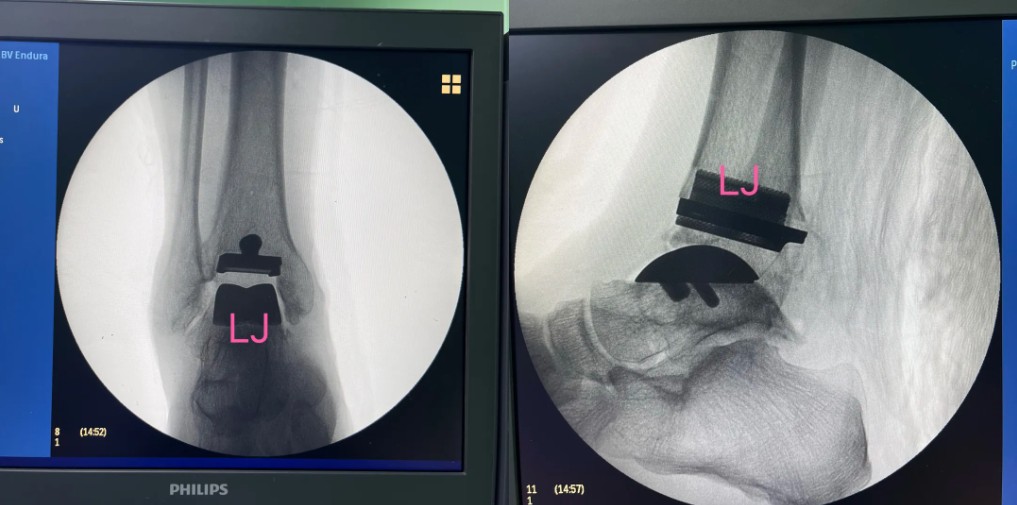

術(shù)后影像

基于患者踝關(guān)節(jié)三維影像數(shù)據(jù),3D打印專屬截骨導(dǎo)板和植入的假體,確保假體與骨骼匹配。

數(shù)字化導(dǎo)板引導(dǎo)下,截骨誤差小于1毫米,極大提升手術(shù)安全性。